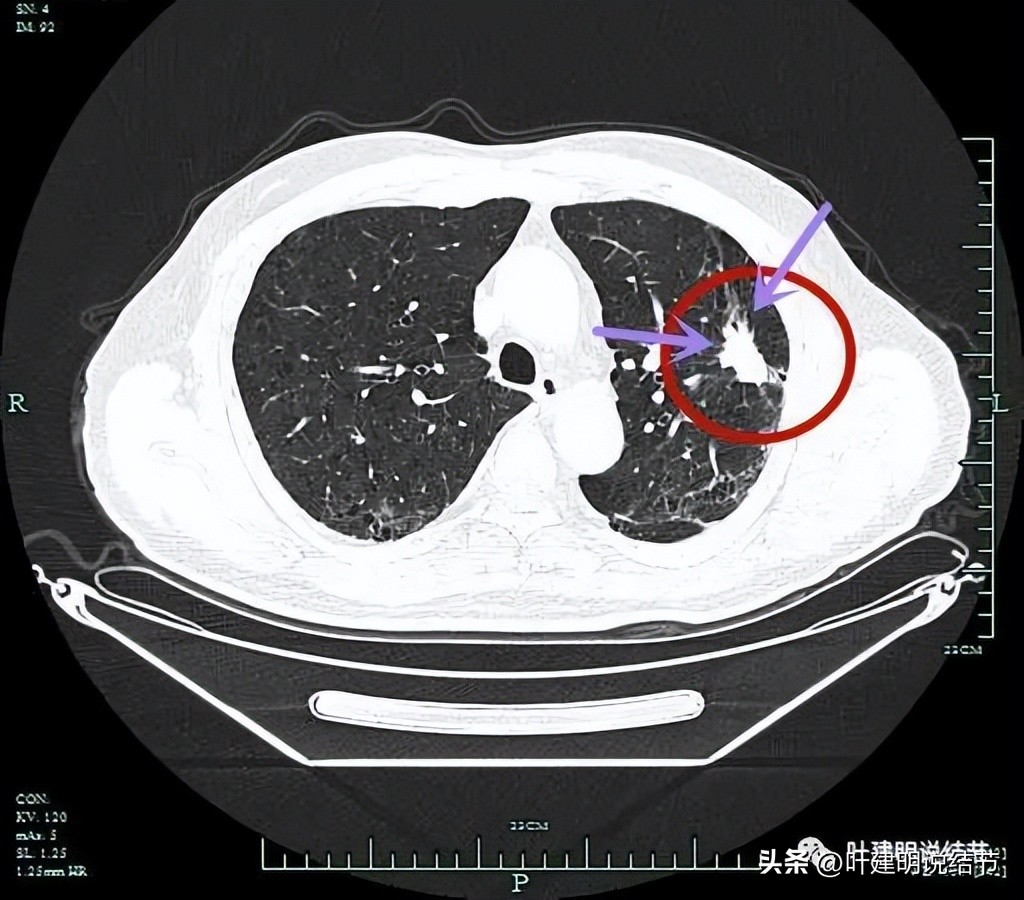

边缘细毛刺。

病灶实性,边上有炎性改变。

此层显得毛刺较长。